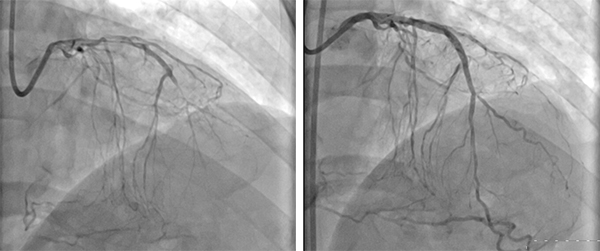

入院后,经进一步的观察发现,兰先生心脏冠状动脉左前降支和左回旋支近端均为弥漫性狭窄,中段完全闭塞;右冠中段狭窄程度达到95%,远段完全闭塞!病情严重,何主任带领心血管内科医疗团队,经过周密准备,制定详细手术计划,先后于1月19日和1月26日成功完成了两次“CAG+PTCA+支架植入术”,通过导管将支架植入左冠状动脉前降支和回旋支关键位置,消除这两支冠状动脉的狭窄症状,经过反复观察造影显示,支架贴壁良好,无残余狭窄,无夹层无撕裂,血管大小及血流状况恢复到正常水平,手术成功!兰先生目前病情恢复良好,待年后再次手术解决右冠状动脉症状之后,即可达到较为满意效果。

术前(左)术后(右)对比